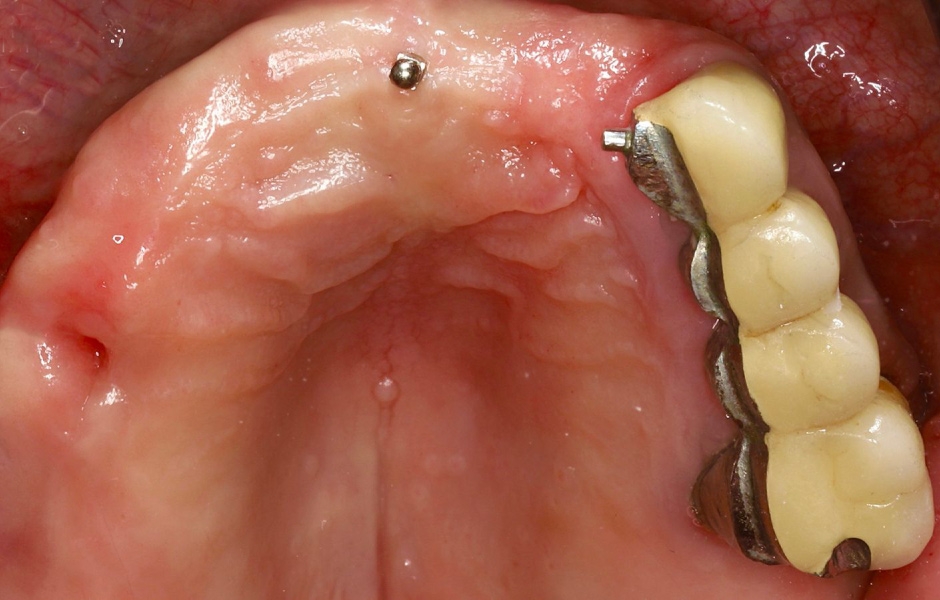

Intraorální vyšetření odhalilo starý můstek, který nahrazoval zuby 23 až 26 a zároveň sloužil ke kotvení částečné snímatelné náhrady s kovovou výztuží. Zuby 22 až 17 byly extrahovány již před delší dobou a alveolární hřeben v této oblasti byl zhojen. Nebyl přítomen plak ani zánět. Zuby vykazovaly mírnou až střední ztrátu attachmentu, ale nebyly pozorovány žádné parodontální léze nebo fraktury kořenů (obr. 5–8).

K dokončení protetického ošetření jsme využili skenovací pomůcku Straumann® RevEX™ Scanbody pro plně monolitický návrh náhrady s kompletně digitálním výrobním postupem. Nejprve byl proveden intraorální sken protilehlého oblouku, následovaný intraorálním skenem ošetřovaného oblouku s přišroubovanými dočasnými abutmenty. Poté byl proveden sken skusu a intraorální sken měkkých tkání s nasazenými šroubovanými abutmenty pro definitivní náhradu. Na provizorní náhradu byly připevněny reverzní skenovací pomůcky Straumann® RevEX™ Scanbody a náhrada byla nasnímána extraorálně. Následně byl navržen a vyfrézován prototyp náhrady a také verifikační šablona. (obr. 45, 46).

Pro kotvení definitivní náhrady byly použity abutmenty Variobase® for Bridge. Materiálem pro výrobu definitivní náhrady byl zvolen monolitický zirkon (obr. 49, 50).

Obr. 8

Obr. 9